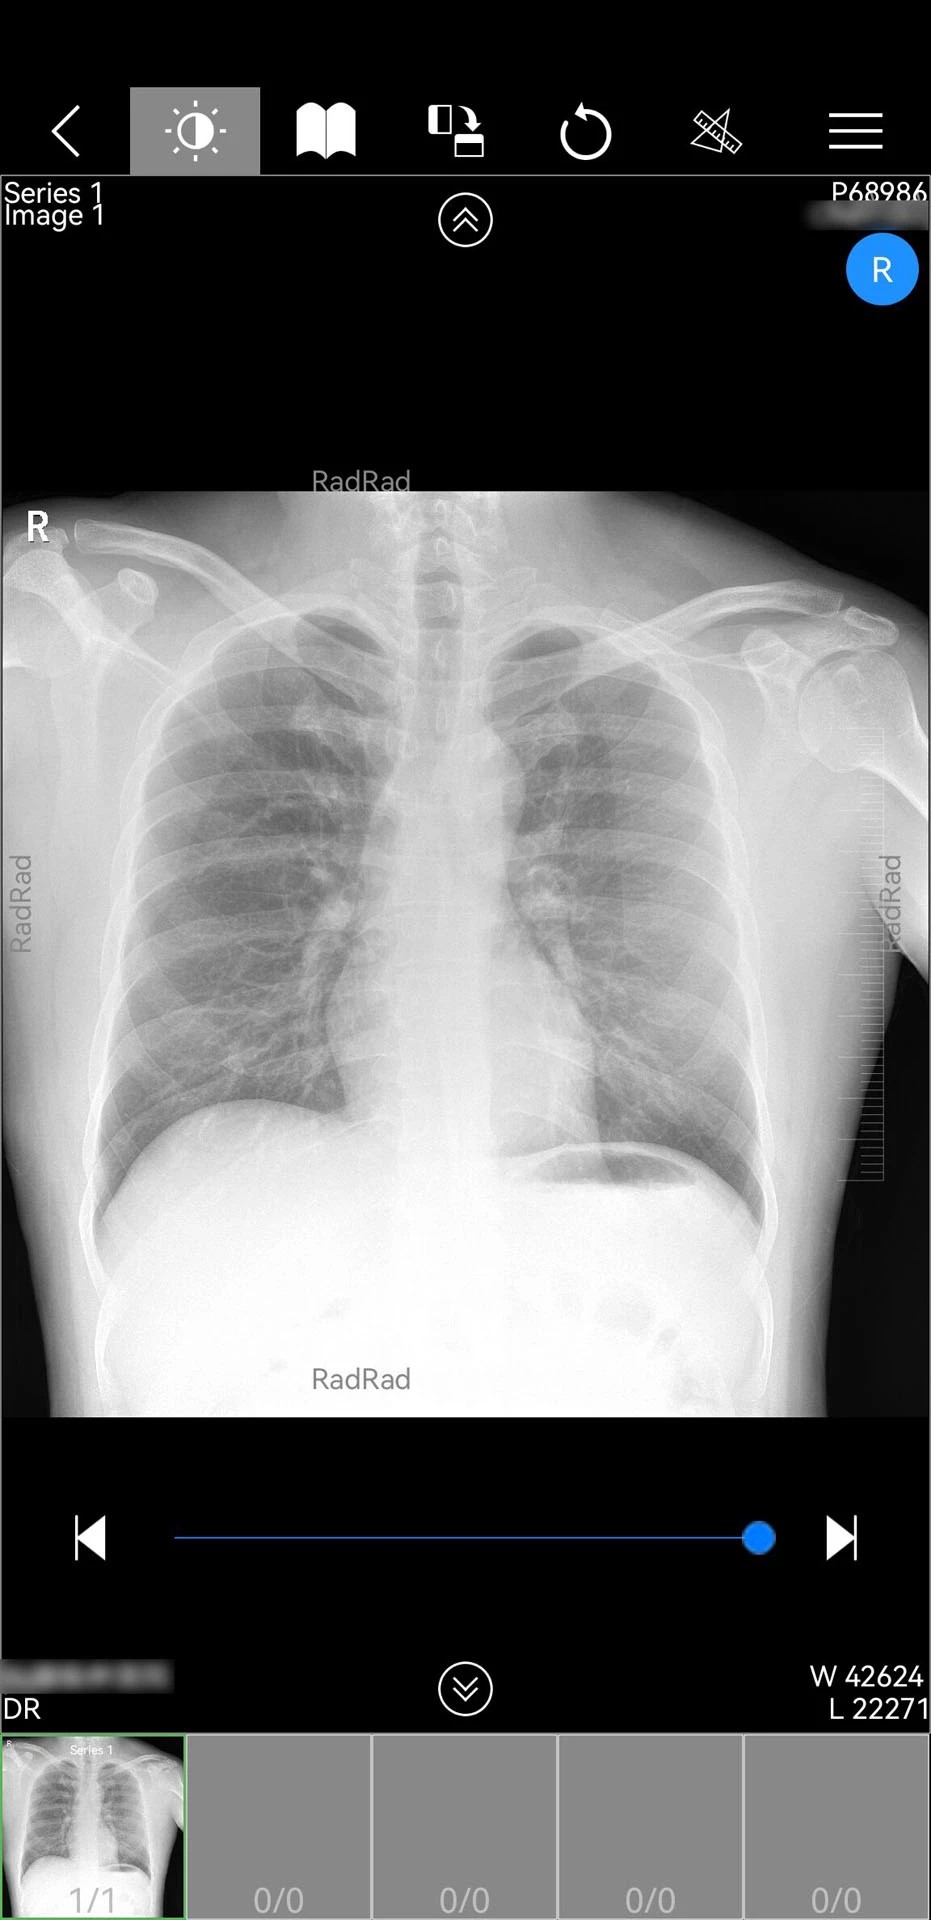

1. 全场景影像支持:支持CT、MRI、X光等主流医学影像的实时调阅,通过三维重建技术将二维影像转化为立体模型,辅助医生精准定位病灶。例如,在肺部结节诊断中,医生可旋转三维模型观察结节与血管的毗邻关系,制定更优手术方案。

1. 极简操作界面:全中文可视化设计,支持滑动、缩放等移动端通用手势。例如,医生可通过双指捏合调整影像对比度,长按影像区域添加标注,操作流程符合临床思维习惯。

1. AI辅助诊断引擎:内置深度学习算法,可自动识别影像中的异常区域并标注风险等级。例如,在乳腺钼靶检查中,AI能标记可疑钙化点,辅助医生发现早期乳腺癌。